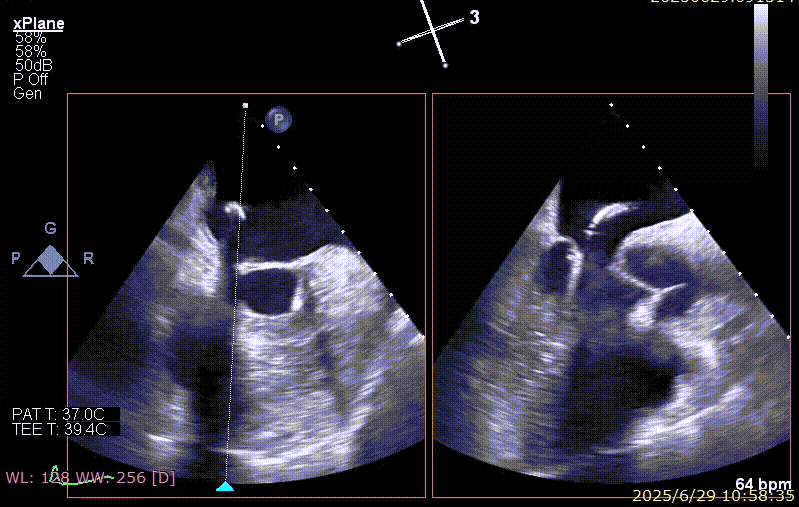

手术步骤

器械植入后二尖瓣 AP 径约 35 mm,CC 径约 39 mm;夹合器固定好、组织桥稳定,前瓣夹闭后瓣叶长度 25 mm,后瓣夹闭后瓣叶长度 7 mm;二尖瓣开放好,瓣口呈大小双孔,二尖瓣瓣口面积约 2.8 cm²,平均压差 1 mmHg,关闭可,二尖瓣反流明显减轻(从术前反流 4+显著改善至 1+),手术全程无需体外循环支持,无需输血,无需射线全超声引导。患者术后第二日回普通病房,患者恢复良好,术后第五日即出院。